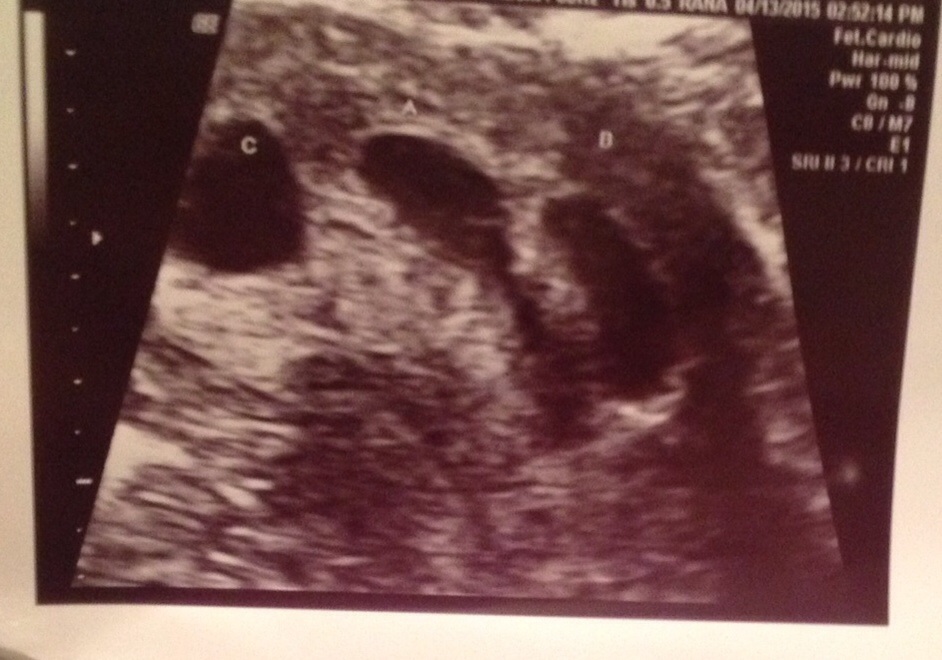

Hey all I've been in the nov 15 board but just found out at my 8w3d ultra sound we are having triplets...my husband an I are in complete shock as we had ultra sound at 5w there was just one empty sac...I did one 5day round of 50mg of Clomid and that's it! We had been trying for a year an half an this is our first.

Are these from your 8week ultrasound? It's weird that it doesn't show any of the babies...at 8 weeks I thought we'd be able to see them. I thought maybe this was your 5 week ultrasound, but that wouldn't make sense because you said you found out it was triplets at 8 weeks.

Eta: I looked closer on pic 1 and 2 and could see more clearly. Why does pic 3 look empty? I'm just curious!

Here are others from same ultra sound

• That ultra sound heart beats were 190,168,157